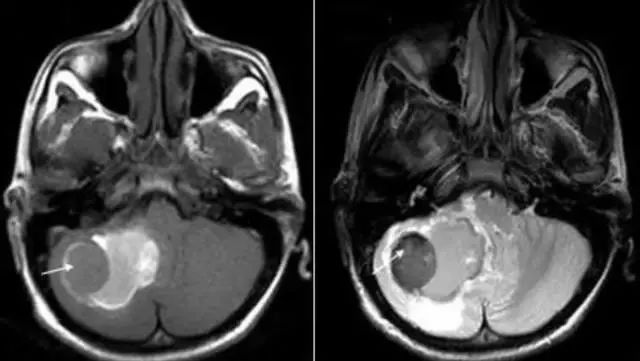

图片

脑出血急性期

核心区域 T1 等信号(左),T2 低信号(右边)